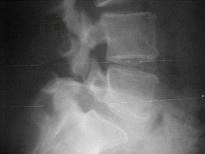

男,50岁,腰背痛,请结合图像,选出最可能的诊断 ( )A、L椎弓峡部不连及L滑脱B、L~S椎间盘突出C、L隐性脊椎裂D、移行椎E...